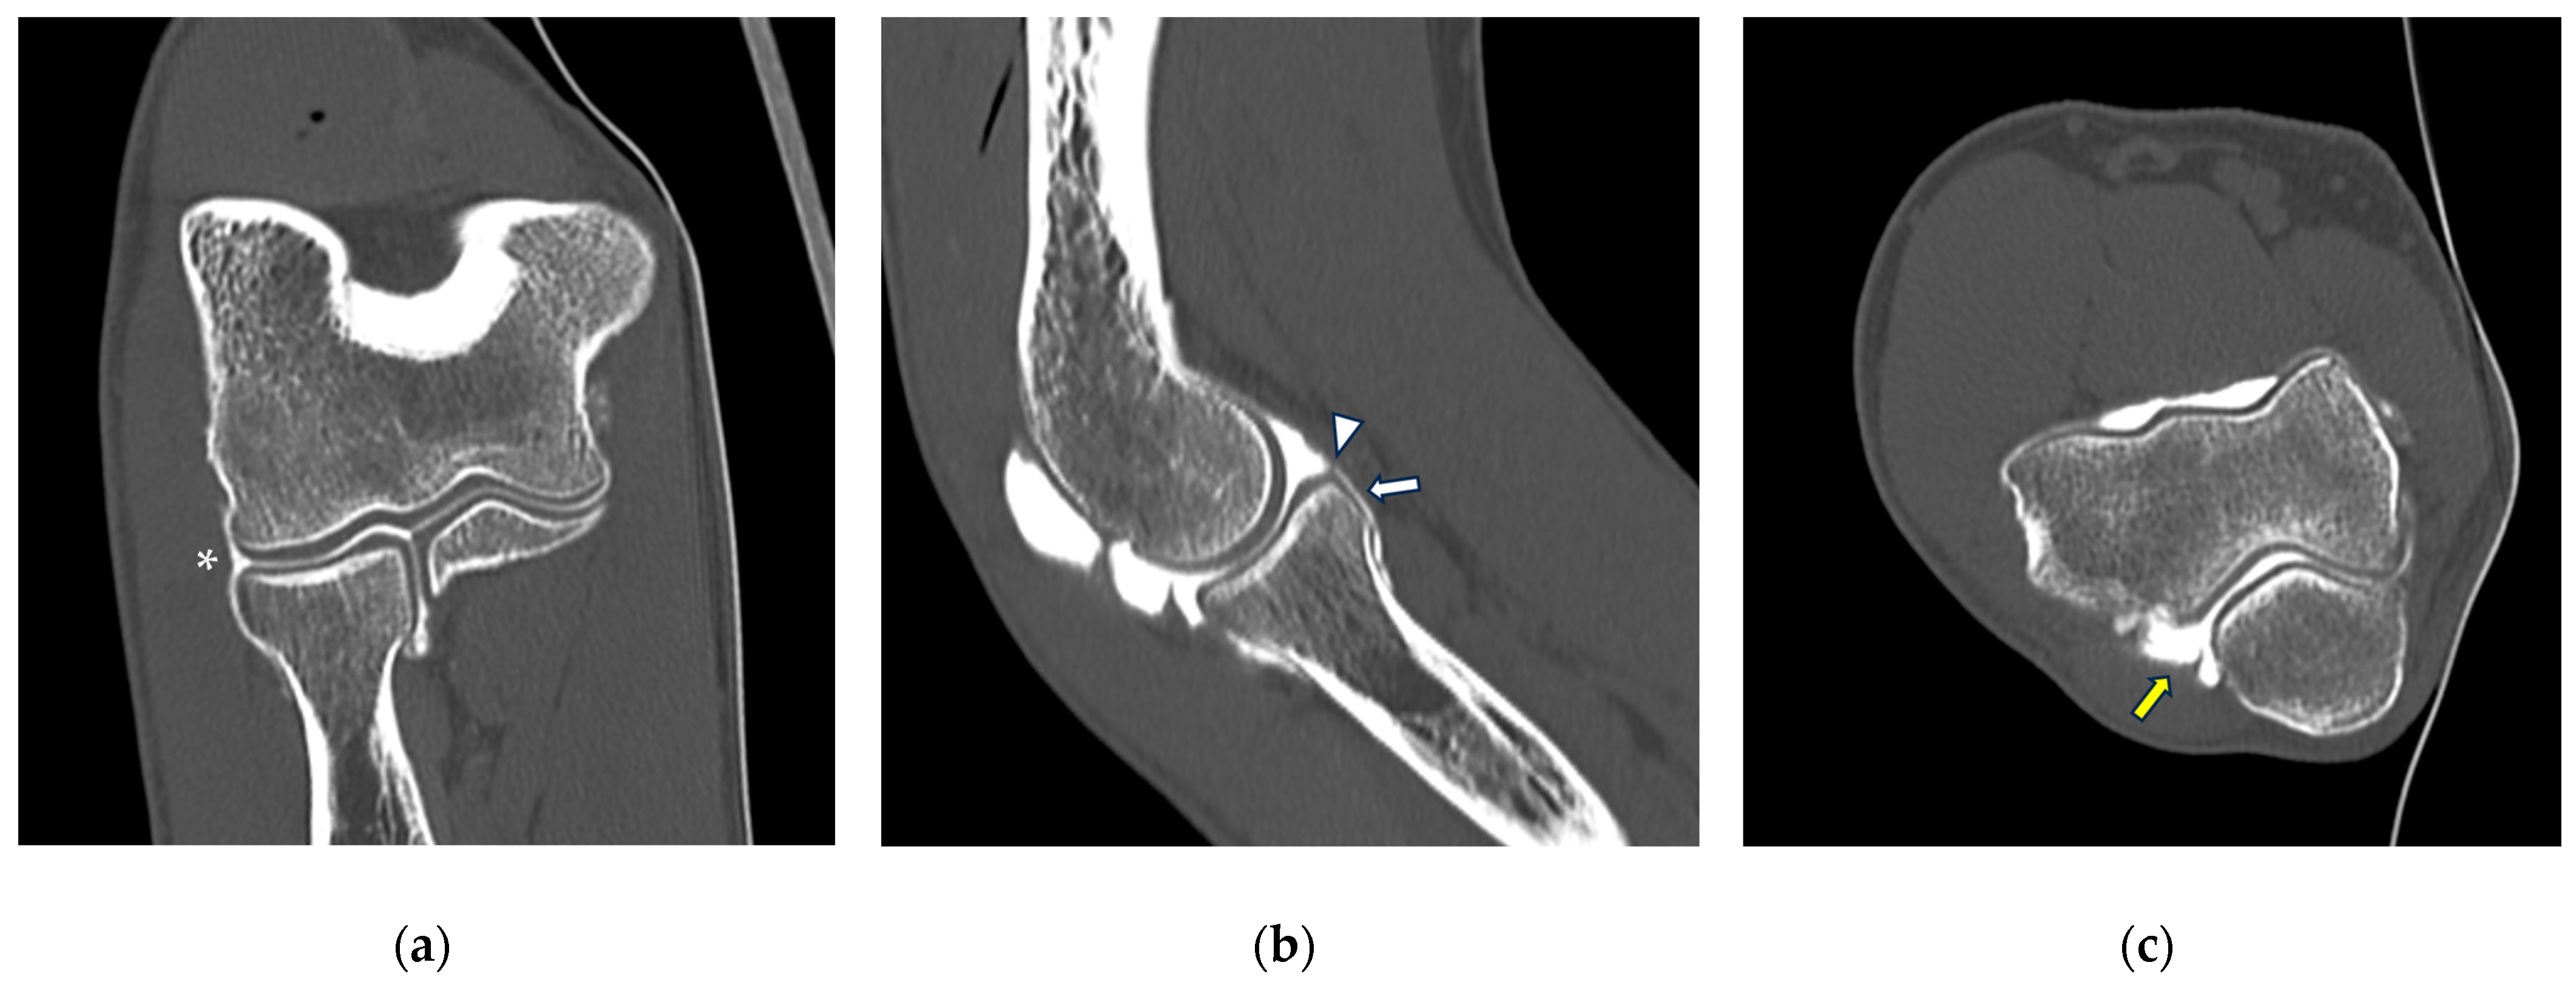

The joint is encapsulated by an articular capsule, a structure that plays a pivotal role in stabilizing the articulation and maintaining joint integrity. The stability of the elbow joint is further fortified by a network of ligaments, each with distinct functions. Indeed, ligamentous structures of the elbow originate as focal thickenings of the joint capsule and are divided into ulnar and radial collateral ligament complexes. As an injury of these elbow stabilizers may lead to elbow instability [28], elbow CT arthrography can provide useful information regarding their integrity. The medial collateral ligament (MCL) complex is made by anterior, posterior, and transverse bundles and acts as the main stabilizer against valgus and extension stress [29], with medial elbow pain being a common symptom in overhead-throwing athletes: in these patients, the medial compartment is subjected to chronic tensile forces that result in inflammation, micro-tearing, and eventually ligament disruption [30]. The lateral collateral ligament (LCL) complex is composed by the radial collateral ligament (RCL), annular ligament, and lateral ulnar collateral ligament (LUCL), stabilizing the elbow against varus and external rotational stress. The annular ligament, encircling the head of the radius, maintains the proper relationship between the radius and ulna during rotational movements. Injuries are more common in the setting of an acute event, such as elbow dislocation, with overuse-related conditions being somewhat more uncommon than in the medial compartment [10]. A comprehensive understanding of the capsule and ligamentous structures is imperative for radiologists, as it forms the foundation for accurate interpretation of CT arthrography, aiding in the diagnosis of traumatic injuries, instability, and pathological conditions affecting the elbow joint. An example of normal CT arthrography anatomy of the elbow is shown in Figure 2.

Figure 2.

CT arthrography of the elbow—normal anatomy. (a) Coronal image shows a regular chondral lining of the radio-humeral, ulno-humeral, and radio-ulnar joints, with no evidence of focal chondral lesions. The articular capsule is not pathologically distended and there is only a physiological amount of contrast in the lateral radio-humeral recess (asterisk), indicating the presence of an intact radial collateral ligament; (b) sagittal image shows an undisplaced annular ligament (white arrowhead), as well as a regular chondral lining of the radial head side and a physiological sliver of contrast in the annular recess (white arrow); (c) axial image shows a physiological amount of fluid in the posterior recess of the elbow (yellow arrow), with no evidence of loose bodies, as well as regular chondral lining of the humerus and olecranon.